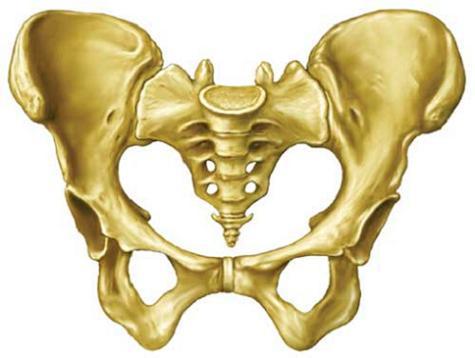

3. Sistema musculoesqueletico

Raúl Rentería Ma